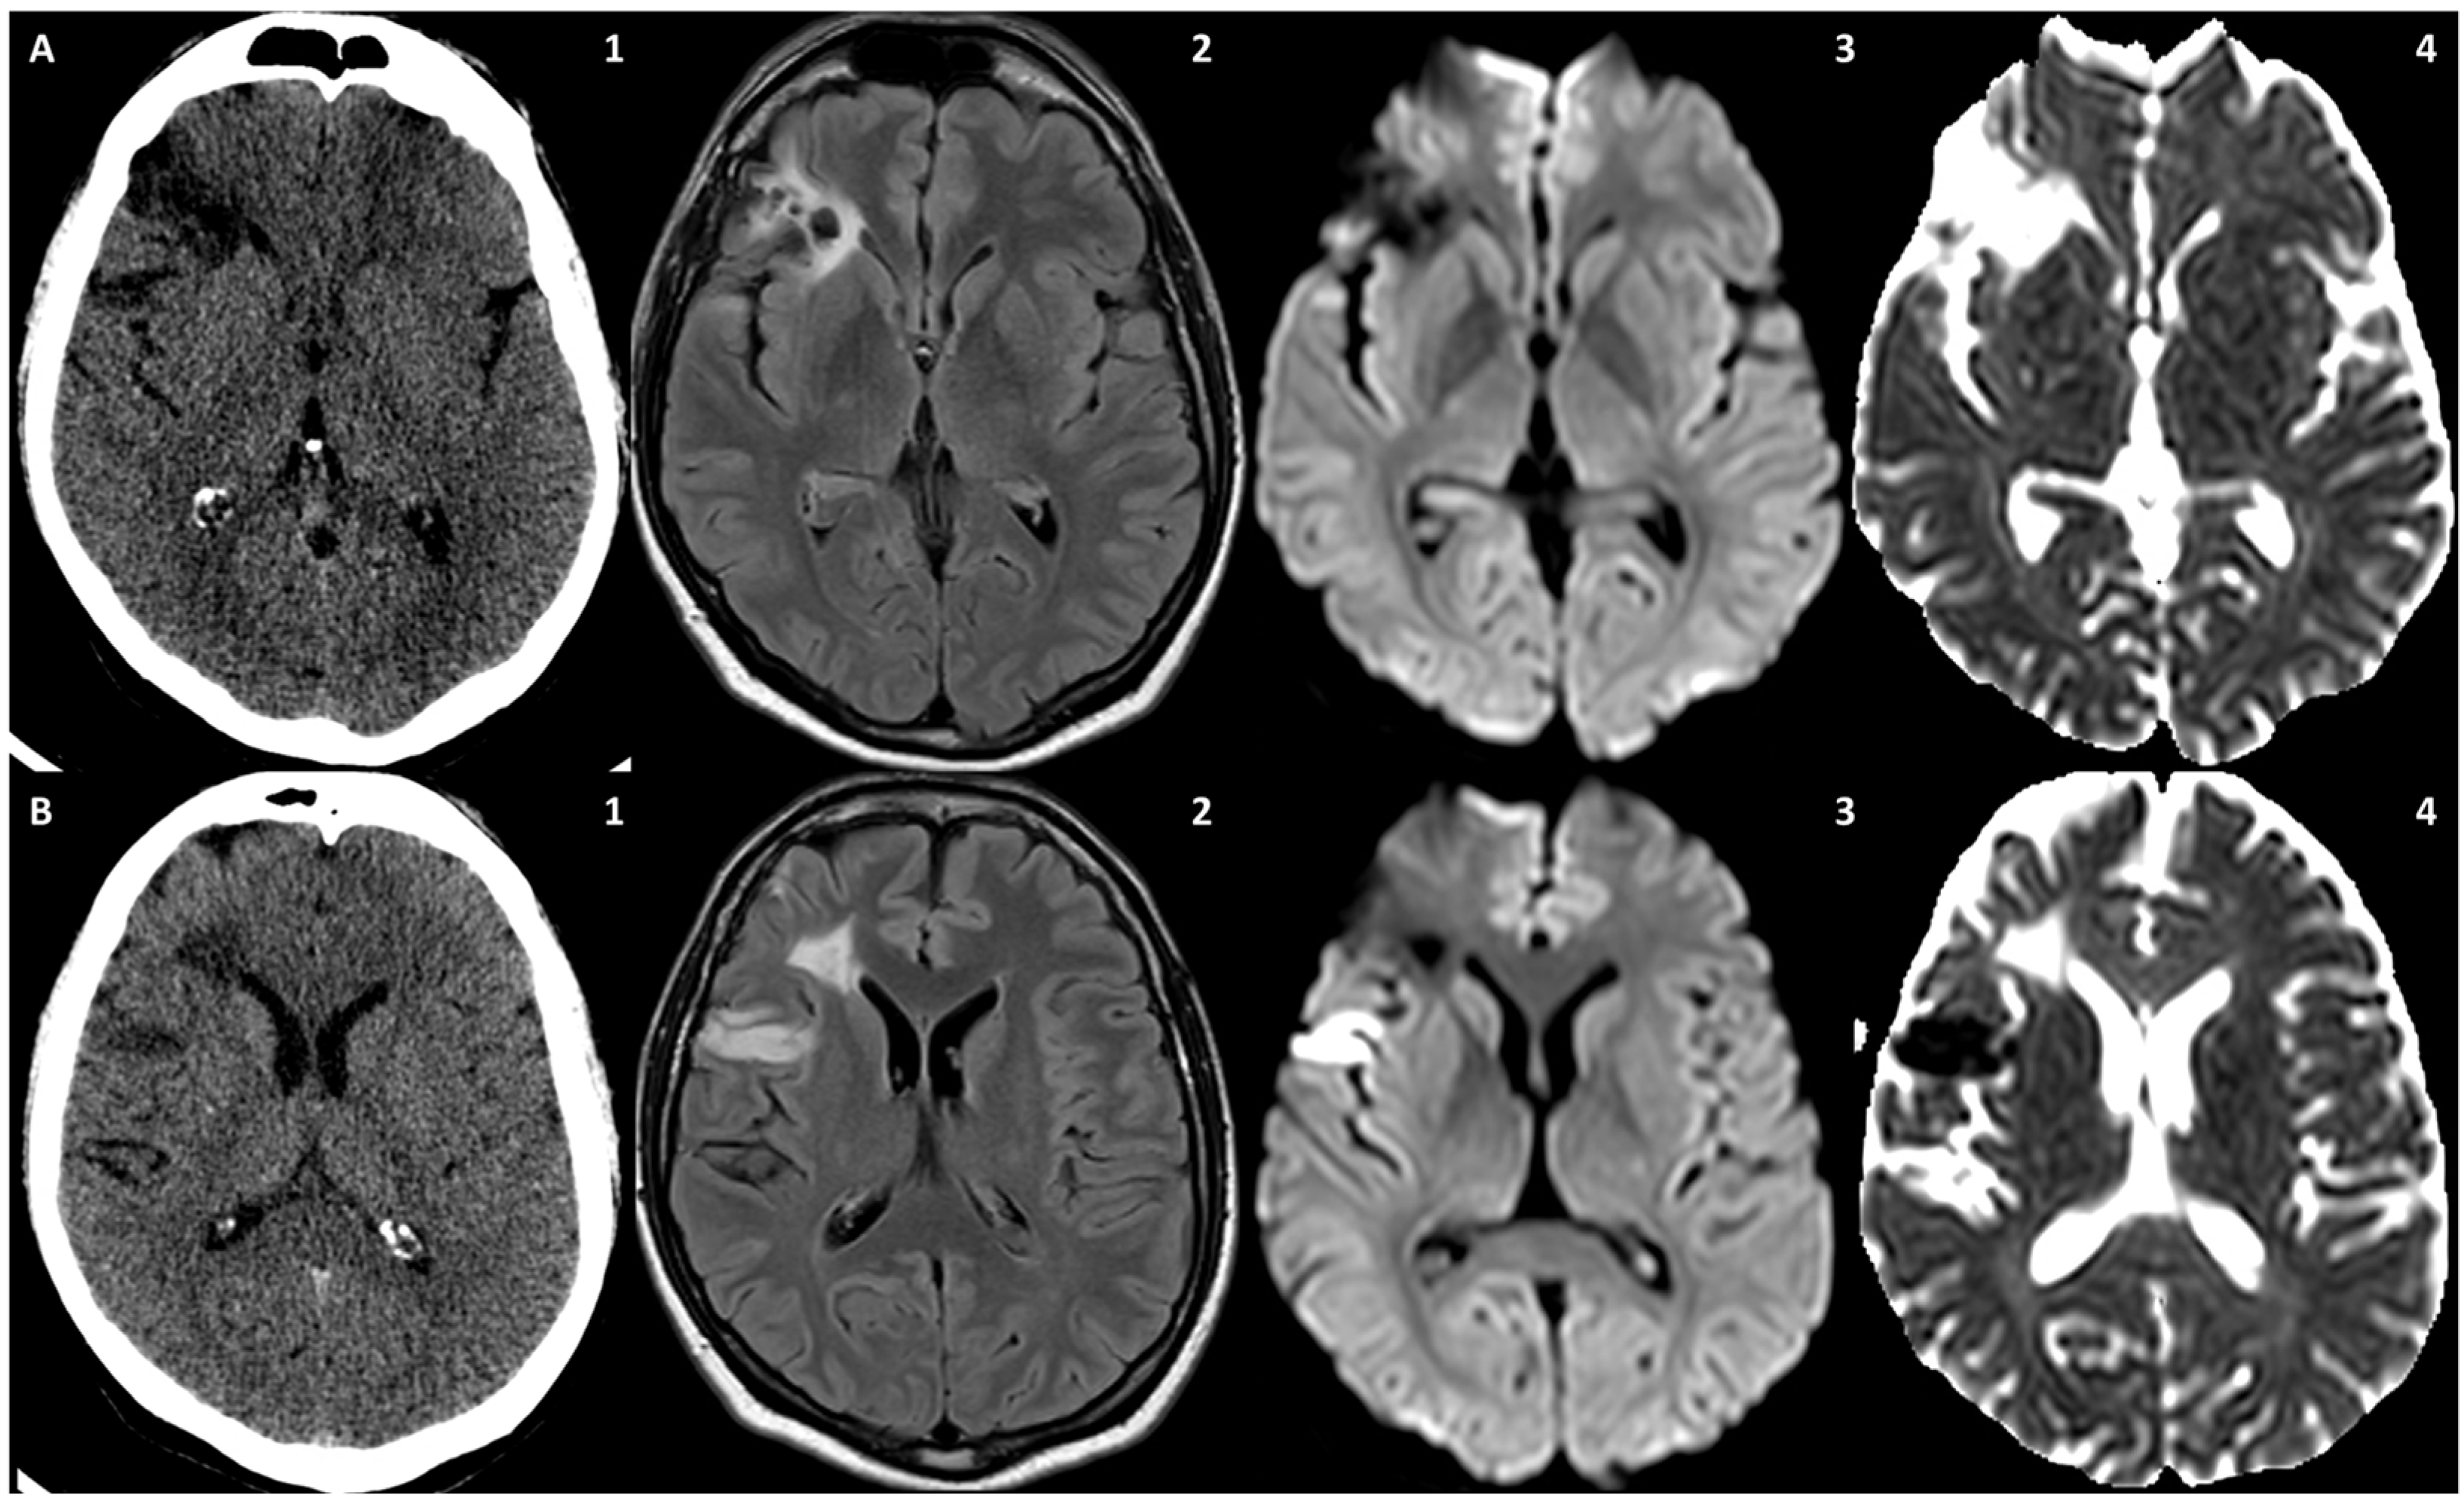

3.1. Case 1

3.2. Case 2